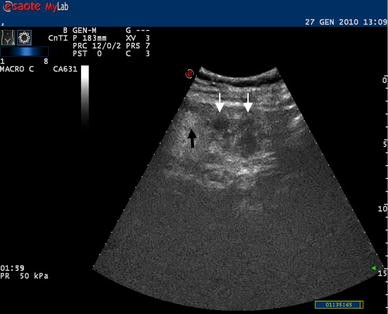

Ultrasonography is the initial imaging test of choice for patients presenting with right upper quadrant pain. Computed tomography CT is recommended for evaluating right or left lower quadrant. I too have just had an ultrasound scan due to abdominal pain around my appendix and having discomfort whilst lying on my right hand side.

Abdominal pain done blood test and ultrasound kindly interpret results Abdominal pain clear ultrasound Abdominal pain taken amoxicillin and metrogyl normal ultrasound. Some Authors assert that the location of pain is a useful starting point and will guide a further evaluation that the American College of Radiology has recommended using different imaging studies to assess abdominal pain based on pain location. Ultrasonography US is recommended to assess the right upper quadrant pain and computed tomography CT is recommended for the right and left lower quadrant pain.

Abdominal pain bloating fatigue abdominal pain beneath sternum bloating gassy pressure b Lower Abdominal pain with lower back pain Cramping pelvic pain back pain 2 days after ovulation pre and post menstral pelvic and leglower back pain Painpressure on right side -abdomen pelvic flank and back Persistanat upper abdominal and mid back paincramping Pelvic pain tailbone pain and sciatica nerve pain. Abdominal ultrasounds are used to check the major organs in the abdominal cavity. These organs include the gallbladder kidneys liver pancreas and spleen.